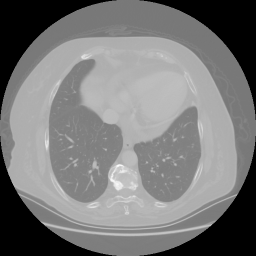

Original VENOUS CT scan

No window - Raw intensity values

Lung window (WL -600, WW 1500 β†’ Low βˆ’1350, High +150)

Mediastinum window (WL 40, WW 400 β†’ Low βˆ’160, High +240)